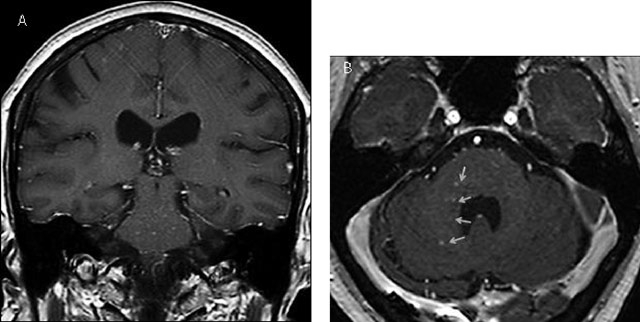

Figure 2

Axial T1 with contrast showing multiple discrete curvilinear lesions in the cerebral white matter of the superior frontal and prerolandic gyrus in both hemispheres.

Figure 3

Coronal (A) and axial (B) contrast-enhanced T1 MRI images after 1.5 years showing new punctate and curvilinear lesions predomanintly in the pons and the right middle cerebellar peduncle (yellow arrows).